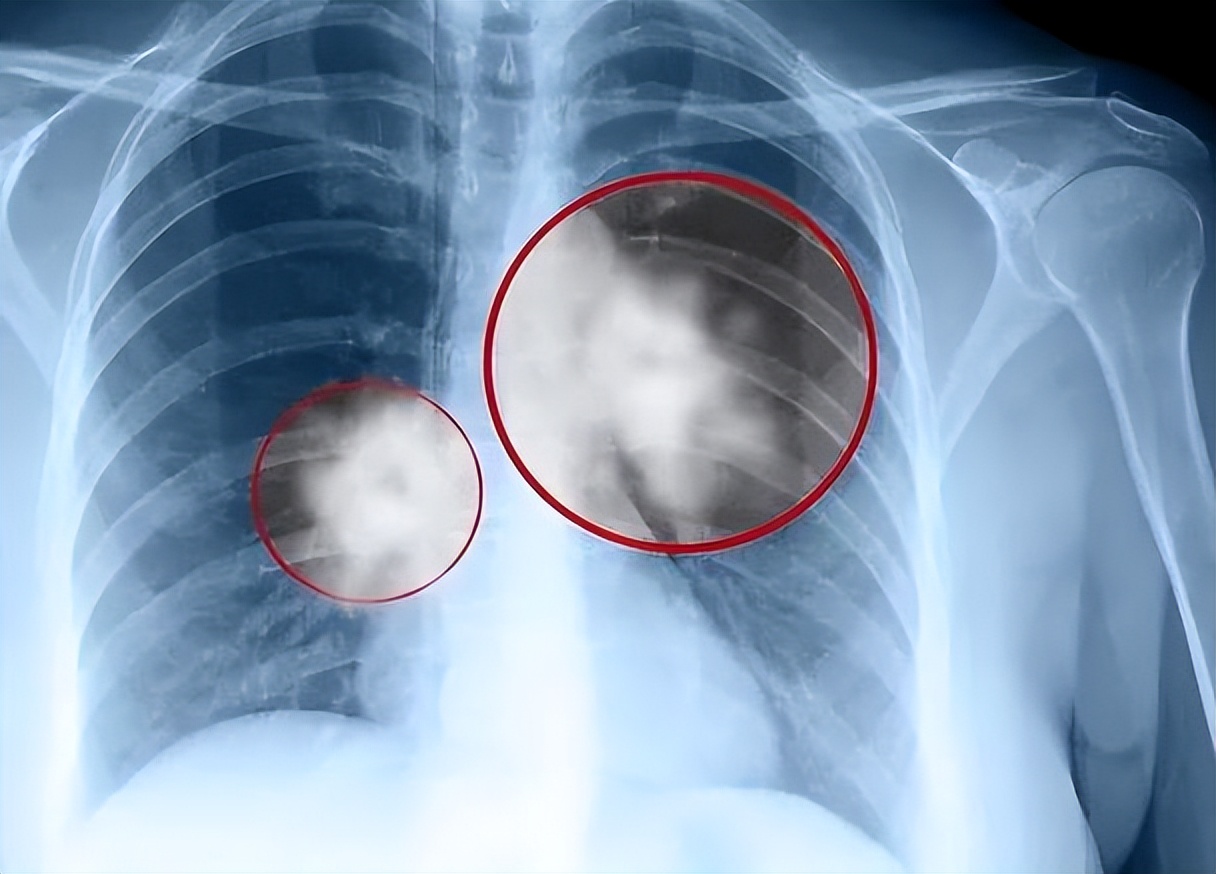

最新数据颠覆认知:肺癌已反超乳腺癌,成为女性第一高发癌。

更危险的是,很多从不吸烟的年轻女性也被盯上,发病增幅远超同龄男性。

别让她为你点的烟和你炒的菜买单当肺癌成为中国女性的头号杀手,这不再是一个单纯的医学问题。